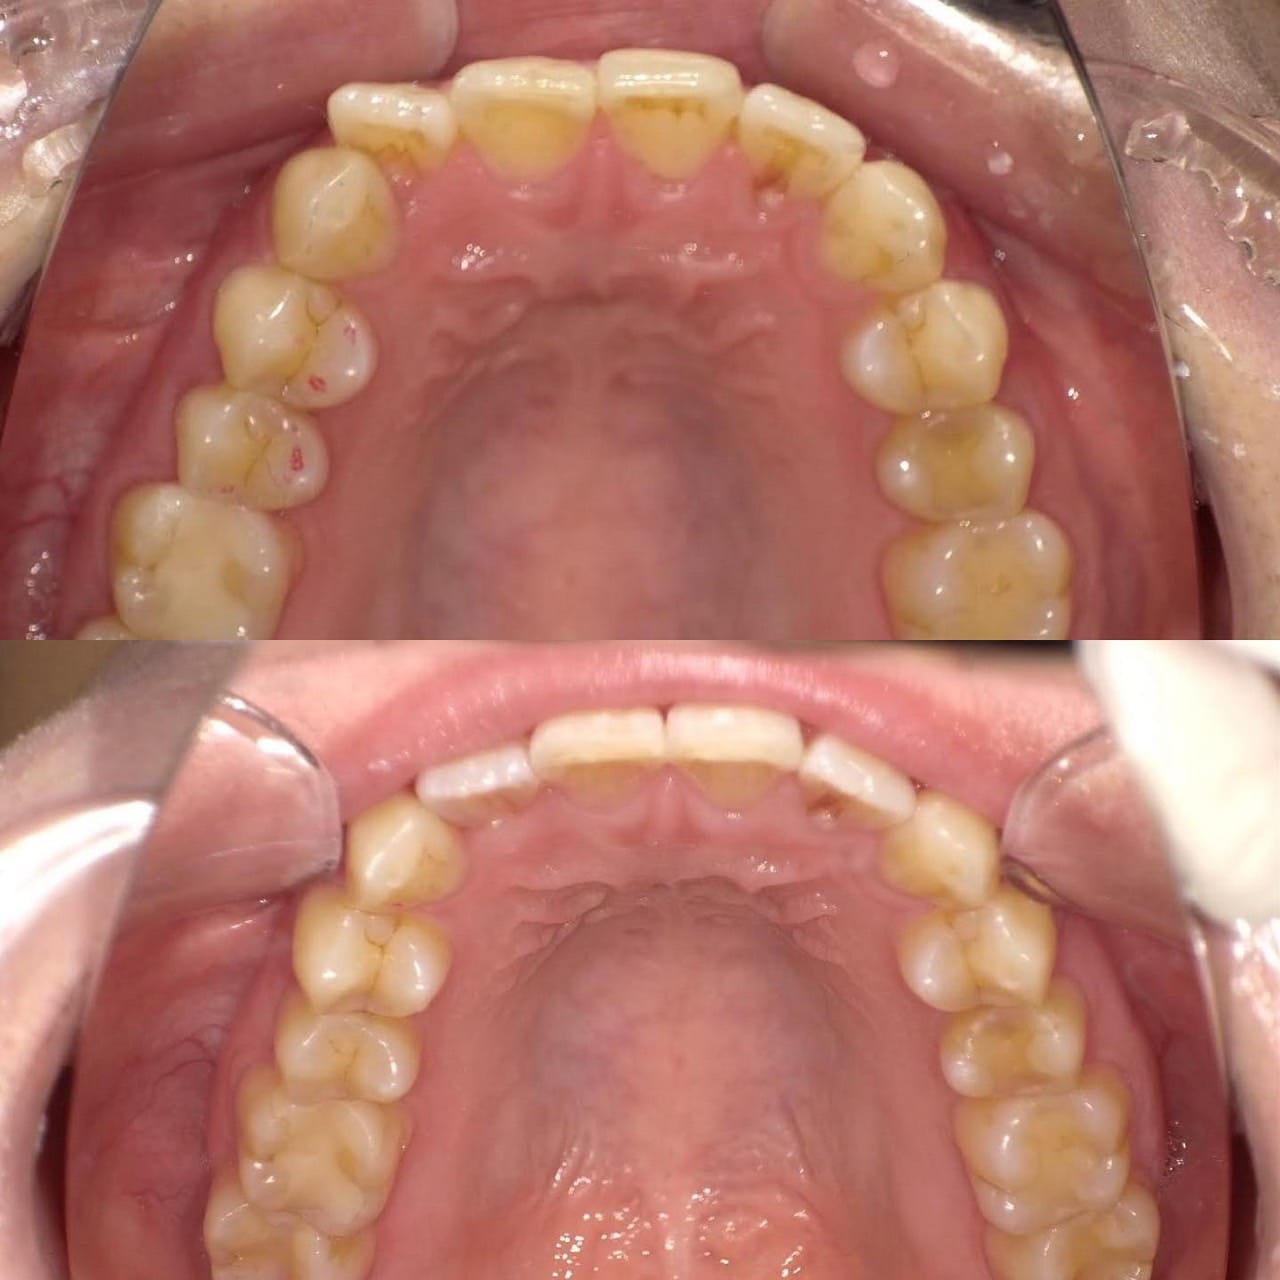

「ずっと放置してしまっていた。今回はちゃんとしっかり治したい」ということで、強い意志をもって来院してくださった患者様の症例です。

インプラント治療、セラミック治療、歯周病治療により、審美性と機能、咬みあわせの再建を行いました。

患者様は咬みあわせの確立により、食事もしやすく、普段の顎関節の状況も良くなり、機能の回復にも満足してくださり、また審美性も喜んでくださいました。

放置期間が長くだいぶ骨が溶けてしまっていたので、前歯部のインプラントは骨の再生療法などが必要だったりしましたが、患者様が治療への前向きな姿勢をだしてくださっていましたので期間も最短で終わりました。

一度放置してしまうと、億劫になってしまってなかなか行動に移すのは難しいと思いますが、少しでも早く治してあげた方が毎日の食事も楽になりますし、お顔の見栄えもお顔の骨格の歪みも改善します。